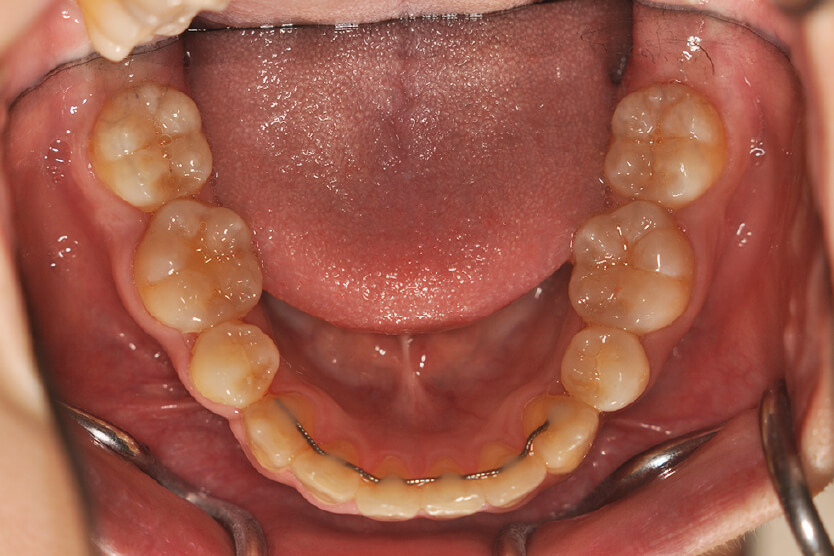

| 治療内容の詳細 | 初診時21歳の女性で、八重歯、歯のがたつき主訴として来院されました。 検査の結果、上下顎前歯部叢生を伴うアングルⅡ級1類不正咬合と診断しました。 治療としては、上下顎左右第一小臼歯を抜歯し、セルフライゲーションブラケット装置(デーモンシステム)とマウスピース矯正装置(インビザライン)で歯の配列を行いました。 治療期間は、1年4か月でした。 |